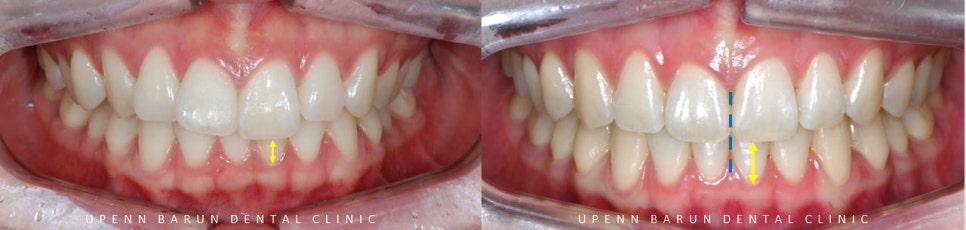

교정 전 후를 비교해보니

교정 전

윗니가 아랫니를 과도하게 덮고 있어

답답해 보였던 치아들이

교정 완료 후

과개교합이 개선되고

아랫니들이 더 잘 보이면서 시원해 보이는 느낌을 줍니다.

또한,

정중선이 일치하면서

치아들이 올바르게 배열된 모습을

확인해 보실 수 있습니다.